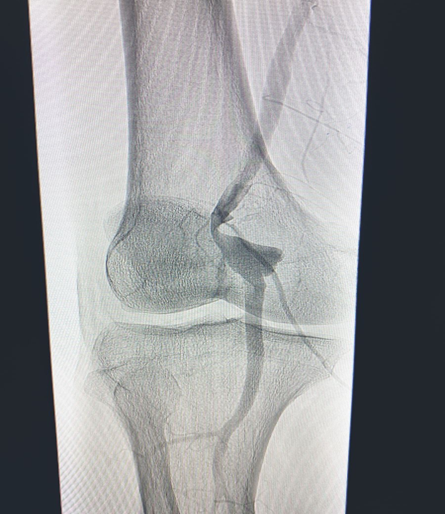

Figure 1: Angio-CT scan in axial incidence showing popliteal artery aneurysm (PPA).

The patient was scheduled to undergo endovascular treatment of the popliteal artery aneurysm. Under general anesthesia, a right common femoral artery was antegrade punctured guided with a duplex ultrasound to perform the whole intervention percutaneously with a 6F 11cm sheat. After the puncture, the Perclose Proglideâ was inserted, in order to preload and guarantee the sealing of the puncture. Then, a 0,035”260cm Terumo â was used to perform the crossing over the distal arteries. The patient was heparinized with 5000UI intravenous in bolus. We performed a right limb arteriography to confirm the popliteal artery aneurysm (Figure 2). The popliteal artery was properly catheterized and we changed the guidewire for an Amplatz 0,035”260cm, in order to place a 11cm 11F sheat. After proper evaluation, two a covered self-expandable 8x100 and 10x75 Merit Wrapsodyâ were placed under roadmap into the distal popliteal artery and proximal femoral artery respectively, and post dilatated with a 8x100 and 10x100 catheter balloon Oceanus figures 3 and 4. There were no endoleaks, and the popliteal artery patency was identified. All the materials were removed, and we completed the final step of the perclose Proglideâ puncture closing. The patient was transferred to the nursery room, being discharged from the hospital two days after the surgery with no complications, femoral, popliteal and podal pulses present bilaterally, taking Rivaroxaban 20mg / day and Clopidogrel 75mg/day. After 1 month the patient was evaluated, presenting no further symptoms, no palpable mass in the right popliteal artery, and was submitted to a Duplex Ultrasound (Figure 5), that showed deep popliteal artery patency, stent patency, reduction of the aneurysm sac and no endoleaks. Furthermore, after one year follow-up, the patient remained asymptomatic, with Duplex Ultrasound showing popliteal artery with stent patency and no endoleaks. (Figure 6).

Figure 2: Arteriography showing PPA.